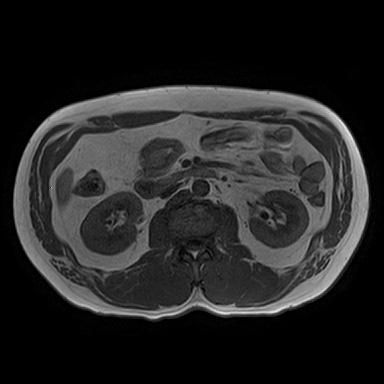

• 비뇨기과를 가시는 것이 맞고, 제공해주신 MRI와 초음파 소견을 종합하면, 양측 신장에 병변이 보이기는 하나 형태가 서로 다릅니다. 한쪽은 비교적 경계가 명확하고 밝게 보이는 병변으로 낭종 가능성이 우선 고려되고, 반대쪽은 내부 신호가 혼재된 형태로 단순 낭종 외의 병변 가능성도 완전히 배제하기는 어렵습니다. 다만 단일 컷 이미지로는 조영 증강 여부, 내부 구조, 혈류 평가가 제한되어 확정 판단은 불가능합니다.

임상적으로 중요한 기준은 단순 낭종인지, 복합 낭종인지, 혹은 고형 종양인지 구분하는 것입니다. 단순 낭종이면 추가 치료 없이 경과관찰이 원칙이고, 복합 낭종이나 고형 병변이면 추가 평가가 필요합니다. 이 구분은 조영증강 CT 또는 조영 MRI에서 보스니악 분류 기준으로 판단합니다.